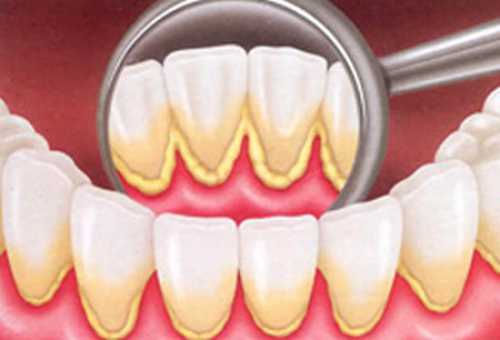

RASPAGEM PERIODONTAL

É o tratamento de gengivas inflamadas e infeccionadas. A doença periodontal causa sangramento na gengiva, mobilidade dos dentes e mau-hálito.

Previamente à raspagem, é usada uma sonda periodontal para determinar a existência e profundidade de bolsas entre os dentes e a gengiva. A raspagem com curetas remove os depósitos de tártaro e placa acima e abaixo da linha da gengiva. O aplainamento alisa as superfícies das raízes de forma que a gengiva possa aderir ao dente novamente